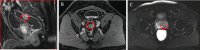

Figure 1.

Sagittal (A) and axial (B) T1 MRI images with contrast showing a hypervascular mass involving the posterior rectum without evidence of extension into the perirectal fat (a T2 lesion). (C) Axial T2 MRI image showing a hypointense lesion in the posteromedial aspect of the peripheral zone of the mid prostate gland (organ confined and without extracapsular extension). Abbreviation: MRI, magnetic resonance imaging.